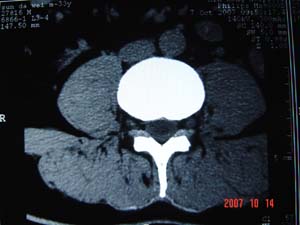

1.l4~5间盘膨出伴突出(中央型)

2.l5-s1后纵韧带钙化.